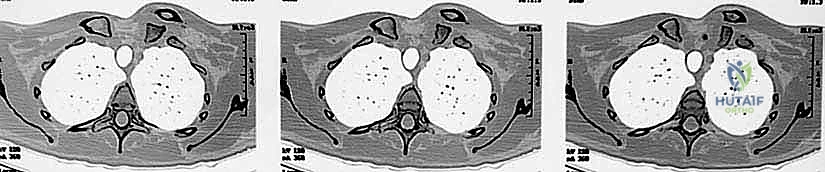

The absolute gold standard, and a non-negotiable prerequisite for surgical intervention, is a high-resolution Computed Tomography (CT) scan. The CT protocol must encompass both sternoclavicular joints and the medial halves of both clavicles to allow for precise contralateral comparison. Axial, coronal, and sagittal reformats, along with 3D surface-rendered reconstructions, are essential. The CT scan definitively differentiates a true ligamentous dislocation from a medial physeal fracture, quantifies the exact degree and vector of displacement, and assesses the integrity of the articular surfaces.

Crucially, in the setting of a posterior dislocation, the CT scan must be performed with intravenous contrast. This "CT Angiogram" phase is vital to delineate the relationship of the displaced medial clavicle to the innominate vessels, the superior vena cava, and the aorta. It identifies pseudoaneurysms, intimal tears, or direct vascular compression that would mandate the immediate presence of a cardiothoracic or vascular surgeon during the exposure. The surgeon must template the anticipated drill hole trajectories for the reconstruction, ensuring they remain safely within the osseous confines of the manubrium and clavicle, directing the drill bit away from the mediastinum at all times.